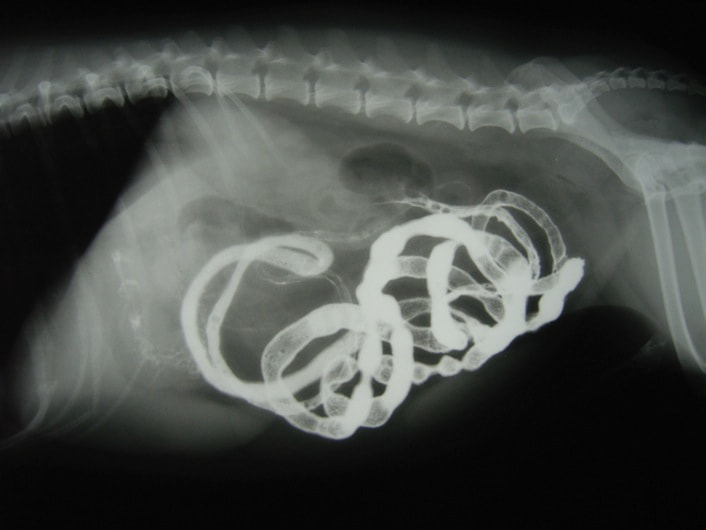

症例3:腸内異物(ヒモ状異物)

雑種猫 4歳 オス

主訴:2時間ごとの嘔吐

◎各種検査結果

・血液検査:著変なし

・レントゲン検査:腸内ガス陰影重度

・バリウム像影検査:造影後2時間、胃からのバリウム排泄なし上記検査結果より、内視鏡検査実施。

・内視鏡検査結果:胃内炎症性病変あり。胃の幽門部から十二指腸領域に向かいヒモ状異物確認。

内視鏡検査結果より、十二指腸領域へのヒモ状異物の可能性があるため、同日腸内異物摘出術実施。

腸内異物摘出術

腸管のアコーディオン様所見

腸内異物摘出

摘出した異物

今回の様なヒモ状の異物は、腸の蠕動運動により腸管を傷つけ、発見が遅れると腸穿孔などの重篤な状態を引き起こします。本症例は、術後1週間程で回復し、現在の経過は良好です。